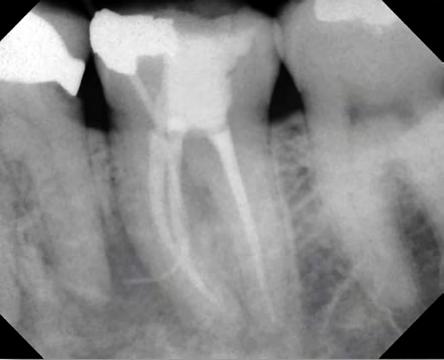

Initial presentation of the patient showed the child sitting comfortably, lightly holding gauze with her anterior teeth. Extraoral evaluation was not significant. Intraoral evaluation revealed generalized dental caries, heme pooling and accumulation in the oral cavity, and a large jelly-like clot protruding from the maxil-

lary left permanent first molar region (Figure 2A). Figure 1: (A) Bleeding localized to lower right quadrant, from distal segment (black arrow) of gingival sulcus of lower right permanent first molar, post-removal of currant jelly-like clot. (B) Imaging revealed intact restorations and no radiolucencies or pathology. Close proximity of distal margin of preformed metal crown on lower right permanent first molar to dental follicle of lower right permanent second molar was noted (white arrow). (C) Area surrounding lower right permanent first molar with hemostasis achieved using local hemostatic measures.

Figure 2: (A) Currant jelly-like clot by extraction site in upper right quadrant. (B) Removal of currant jelly-like clot. (C) Extraction site with hemostasis achieved using socket curettage and local hemostatic measures.

Supraperiosteal infiltration local anesthesia in the form of 2% lidocaine with 1:100,000 epinephrine was administered at the extraction site. The clot was removed, and the socket was curetted and irrigated with saline solution (Figure 2B). Examination of the socket revealed visualization of the unerupted crown of the permanent maxillary left second molar serving as the distal wall of the socket. After 30 minutes of finger pressure, small loose clots formed but were not adhering, and bleeding continued. The socket was curetted and irrigated, and an absorbable gelatin dental sponge was gently placed in the extraction site. Hemostasis was achieved with finger gauze pressure. The patient was discharged and followed up at the outpatient dental clinic the next day with no residual pain or persistent bleeding issues (Figure 2C).

Figure 3: (A) Currant jelly-like clot encompassing exfoliating tooth #B. (B) Intraoperative radiograph revealing erupting tooth #4 and exfoliating tooth #B. (C) Extraction site with hemostasis achieved using curettage and local hemostatic measures.

In the first case described, a unique formation of a liver clot developed following placement of a PMC; in the second, following an extraction; and in the third, the result of repeated irritation from an exfoliating tooth on a medically complex patient taking enoxaparin. Although the preceding events of liver clot formations in these cases were different, similarities are noted. In all three cases, the children were in the mixed dentition phase, and there were dental follicles or unerupted teeth directly adjacent to the sites of uncontrolled bleeding. As a tooth develops, the dental follicle surrounds the enamel organ and dental papilla. It provides nutrition to the developing tooth and has a

rich blood supply in order to do so. This rich blood supply may have been a contributing factor to the formation of the liver clot in these cases.[10]

Hemorrhage following seating of a PMC is uncommon due to closure of the soft tissue at the gingival sulcus. However, a sharp edge of a crown may act as constant irritation, preventing normal clotting and healing. The radiograph of the first case reveals the PMC was also near the dental follicle of the permanent right mandibular second molar and may have impinged on the vasculature, causing persistent bleeding. In the second case, lack of pressure may have been the main contributing factor for the abnormal clotting. However, during extraction of the first permanent molar, there may have been possible traumatic impingement of the adjacent dental follicle, causing persistent bleeding. The unerupted crown also may have been an inadequate surface for clots to adhere. In the third case, the repeated trauma of an exfoliating tooth crown meant constant reinjury to the surrounding tissue and, possibly, the erupting tooth follicle.